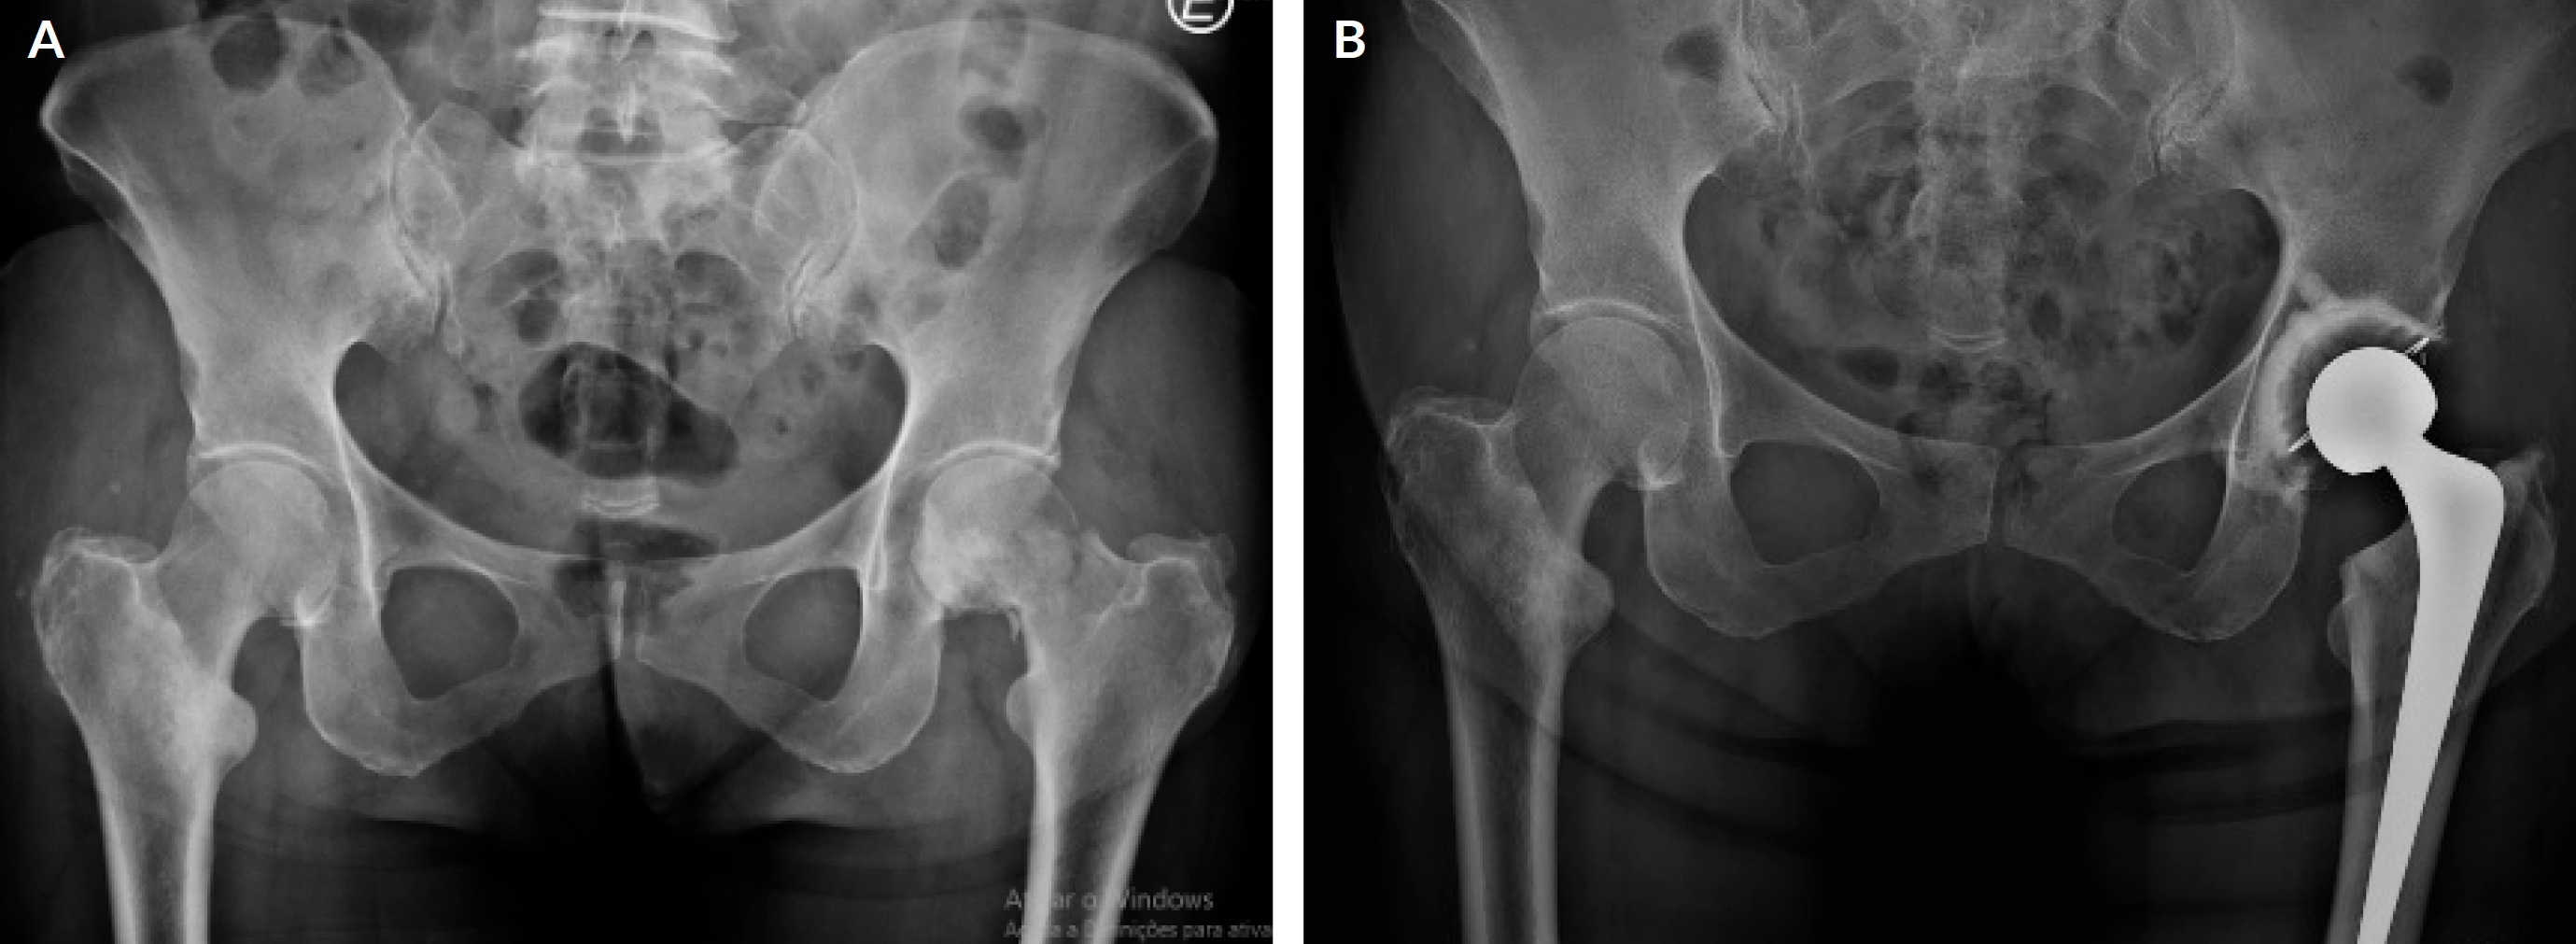

Others may require surgical stabilization (Figs. 1A, B and C) or replacement of arthroplasty (Figs. 2A and B), especially when mechanical failures are present, such as in impending and actual fracture.13,14 In these patients, surgery aims to reduce pain, restore function, and improve quality of life.15 The type of intervention is variable and may be influenced by tumor stage, estimated patient longevity, predicted postoperative functional outcomes and the likelihood of a fracture.